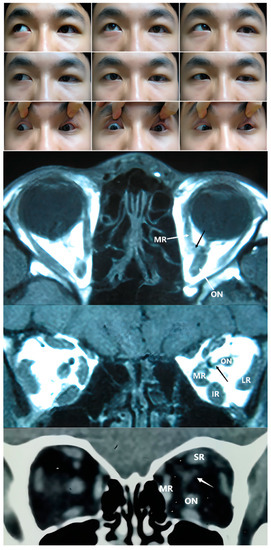

Figure 3. Top Panel: Nine gaze photograph of Case 8 showing a 35 PD of left hypotropia, -3 limitation in OS abduction, and -4 limitation in OS supraduction. The left inferior lid margin was 2 mm lower than that within the right eye. Bottom Panel: Coronal (left) and axial CT of Case 9 showing a unilateral anomaly of EOM bands connecting medial rectus (MR) and inferior rectus (IR) in the left eye, as well as muscular slip between the medial rectus and optic nerve (ON). IR: inferior rectus; LR: lateral rectus.

The third type of case consisted of an abnormal connection zone among the recti, with or without ON involvement. Compared with type 2, the type 3 cases were usually more distinct and identifiable. There was no significant difference in the probability of specific rectus involvement, with the five type 3 cases showing muscular bands connecting two or more recti, as shown in Table 1 and Figure 3. Khitri and Demer et al. [10] reported that abnormal vertical, horizontal, or varied directional connections, as well as levator–trochlear bands, were observed in their series of 12 cases. In the case series presented by Kightlinger et al. [13], an isointense thin tissue band coursing from the temporal edge of the SR to that of the IR was observed in all seven cases. As based on anatomical findings [16], the major vertical and horizontal anomalies observed appeared to involve duplications of the LR and SR muscles, a bifid insertion of the MR, and the absence of ERMs. Wide variations in ERMs and the directions of abnormal bands have been reported in previous studies. Overall, the SR appears to be more frequently involved [20,22,23].